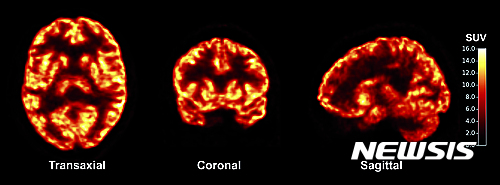

【 AP/뉴시스】미국 예일대 연구팀은 20일(현지시간) 학회지에 발표한 논문을 통해 살아있는 뇌의 신경세포 연결체 시냅스를 촬영하는데 성공했다고 보고했다. 사진은 연구팀이 개발한 기술로 살아있는 뇌를 다양한 각도에서 찍은 사진. 2016.07.21

미 예일 대학 연구진이 살아 있는 뇌의 이 시냅스를 촬영할 수 있는 새로운 기술을 개발해냈다고 20일(현지시간) 보고했다.

PET 스캔(양전자방출 단층촬영)을 이용한 이 기술은 아직은 실험 단계이긴 하지만 언젠가는 많이 발생하고 있는 뇌질환 환자들의 시냅스 기능을 관찰할 수 있게 될 가능성을 보여주고 있다.

예일 대학 연구팀은 트레이서(인체 내부 관찰에 이용되는 방사성 화합물)를 인체 내에 주입해 뇌의 시냅스에서 발견되는 특정 단백질과 결합하게 한 뒤 PET 스캔으로 시냅스를 측정할 수 있는 기술을 개발했다. 트레이서와 결합한 시냅스는 밝게 빛을 내는 반면 시냅스가 없는 부분은 어둡게 나타나는 것을 이용해 시냅스의 수를 측정하는 것이다.

연구팀은 10명의 건강한 자원봉사자와 간질 증세를 보이는 3명의 환자의 뇌 속 시냅스 밀도를 보여주는 뇌지도를 만들었다. 그 결과 건강한 사람의 뇌에 비해 간질 환자들의 뇌에서는 간질과 연관된 뇌 영역에서 시냅스 숫자가 줄어든 것이 밝혀졌다고 연구팀은 20일 '사이언스 중개의학'(Science Translational Medicine) 저널에 게재된 연구 결과에서 밝혔다.